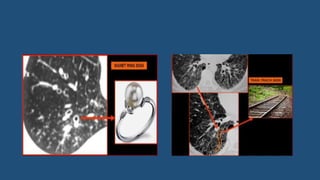

Bronchiectasis

• Bronchiectasis is defined as localized bronchial dilatation.

• The diagnosis of bronchiectasis is usually based on a combination of

the following findings:

• Bronchial dilatation (signet-ring sign, tram track sign)

• Bronchial wall thickening

• Lack of normal tapering with visibility of airways in the peripheral lung

• Mucus retention in the broncial lumen

• Associated atelectasis and sometimes air trapping